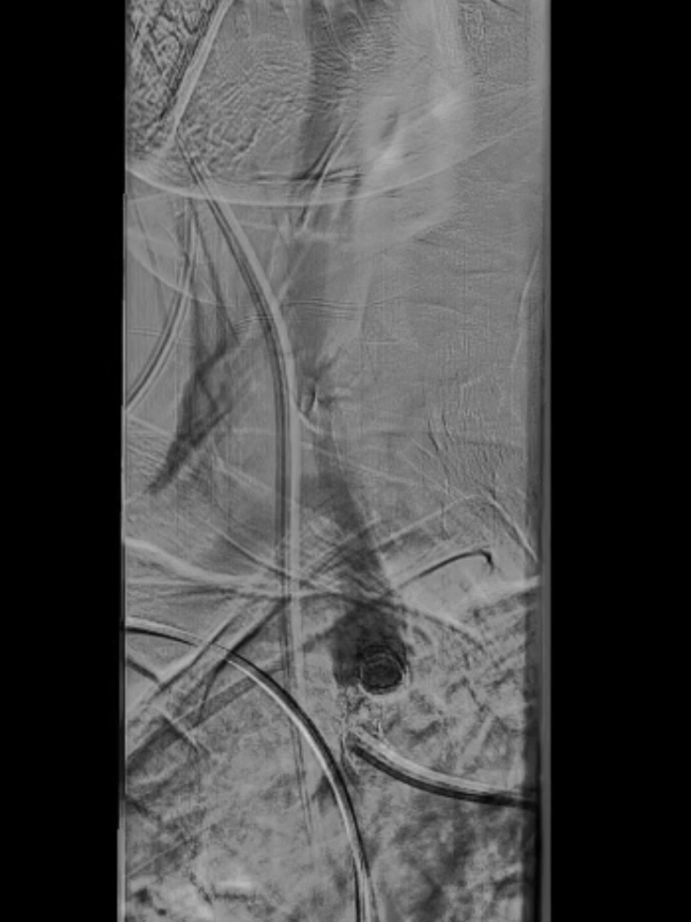

脑保护措施:更换加硬导丝后,采用Filterwire保护伞及0.018导丝选入右颈总动脉,进一步送入右颈内动脉释放保护伞。

跟进长鞘至无名动脉起始

Filterwire 3.5-5.5 保护伞

导丝选入右颈总动脉内

导丝选入右颈内动脉

放置保护伞